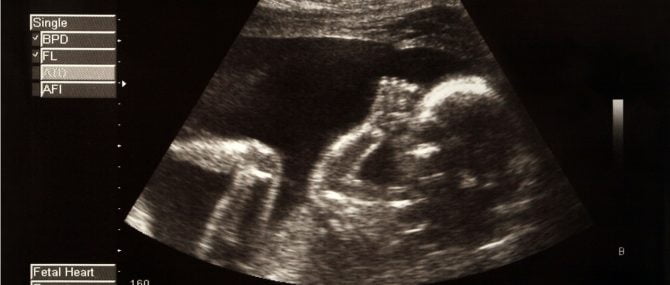

Échographies du foetus

L'échographie est une technique de diagnostic par image qui fonctionne par des ultrasons émis par une sonde. Les ultrasons pénètrent dans la peau (pour faciliter ce processus on utilise un gel aqueux) et elles permettent de voir le foetus, qui est reflété sur l'échographe.

Il s'agit d'un des examens les plus importants lors de la grossesse et qu'il faut pratiquer régulièrement pour s'assurer que tout est normal et que le foetus suit une évolution normale.

Il y a deux types d'échographie:

- L'échographie intra-vaginale

- elle est réalisée lors du premier trimestre de gestation, et bien qu'elle soit plus désagréable pour la femme, elle permet d'obtenir des images beaucoup plus précises.

- L'échographie abdominale

- elle est réalisée pendant les deux derniers trimestres de la grossesse. Normalement il est conseillé de se rendre à cette échographie avec la vessie pleine, afin que l'image se voit mieux.

Grâce à ces examens, on peut déterminer le sexe du bébé avant la naissance, la position dans laquelle se trouve le foetus, la quantité de liquide amniotique, l'évaluation du placenta, la présence d'anomalies morphologiques, etc.

Habituellement, on réalise trois échographies au cours de la grossesse, une par trimestre, concrètement les semaines 12, 20 et 36. Cependant, il est possible de réaliser plus d'échographies si le médecin le juge nécessaire.

Actuellement, mise à part l'échographie classique en 2D, il existe des échographies 3D et 4D qui permettent d'obtenir une image plus réaliste du foetus.